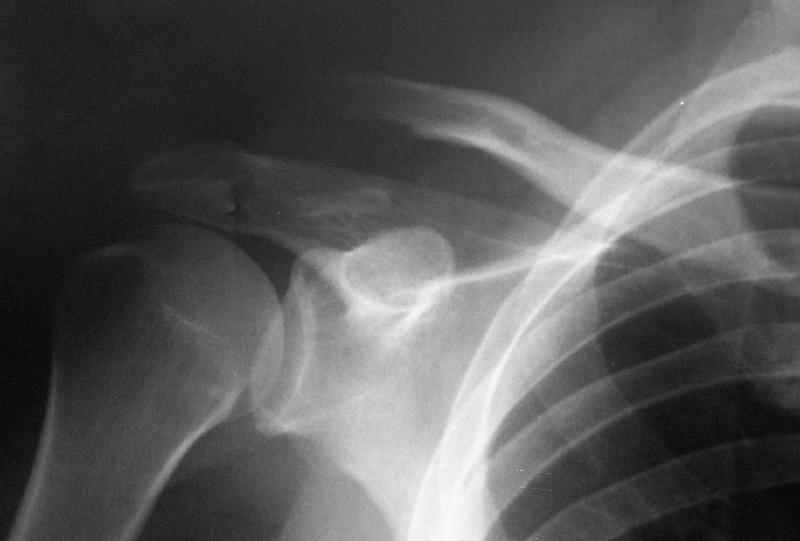

Судя по представленному снимку - существует дистальный фрагмент, который замечательно, вроде бы, связан с акромионом... Что мешает "пришпилить" проксимальный к дистальному и закрепить его при помощи спиц? или как-то по иному (аппарат?)... В любом случае зачем пока идти большим разрезом на ключично-клювовидную связку? почему не пойти от меньшего?

"Толкатель" - укороченная спица с упором. На первичных снимках - оскольчатый перелом, отдельный фрагмент с местом прикрепления кл-кл связки сместился каудально.

Первично правильно сопоставленный перелом (небольшой разрез, спицы) привел бы к тому, что костный фрагмент, отрванный ключично-клювовидной связкой, лег аккурат под своим ложем и тесно к нему... то бишь в итоге сросся бы без проблем... (кстати на вашем снимке костный фрагмент "оскольчатого перелома" консолидирован... то есть даже достигнутая вами несостоятельная фиксация привела к приростанию авульзионно оторванного

фрагмента)

То, что было представлено на вашем снимке - ... - создается впечатление что никакой консолидации в области перелома (основного) достигнуто не было...

Я бы назвал данный перелом как перелом с костной авульзией ключично-клювовидной связи... Потому как данный фрагмент лежит вне основной зоны перелома...